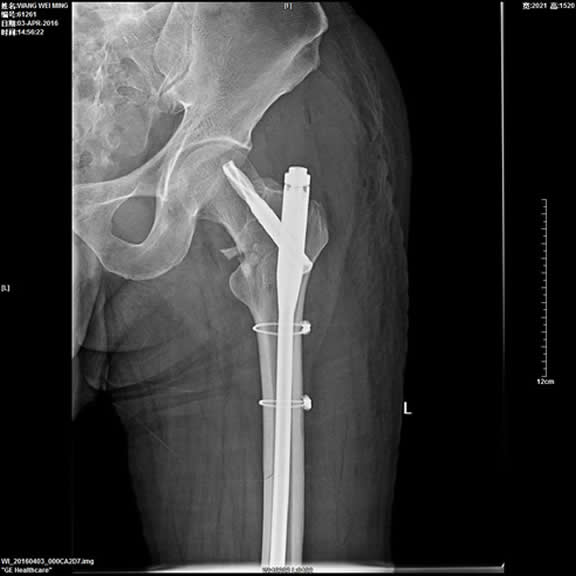

4、股骨上段骨折微创内固定手术(PFNA)。